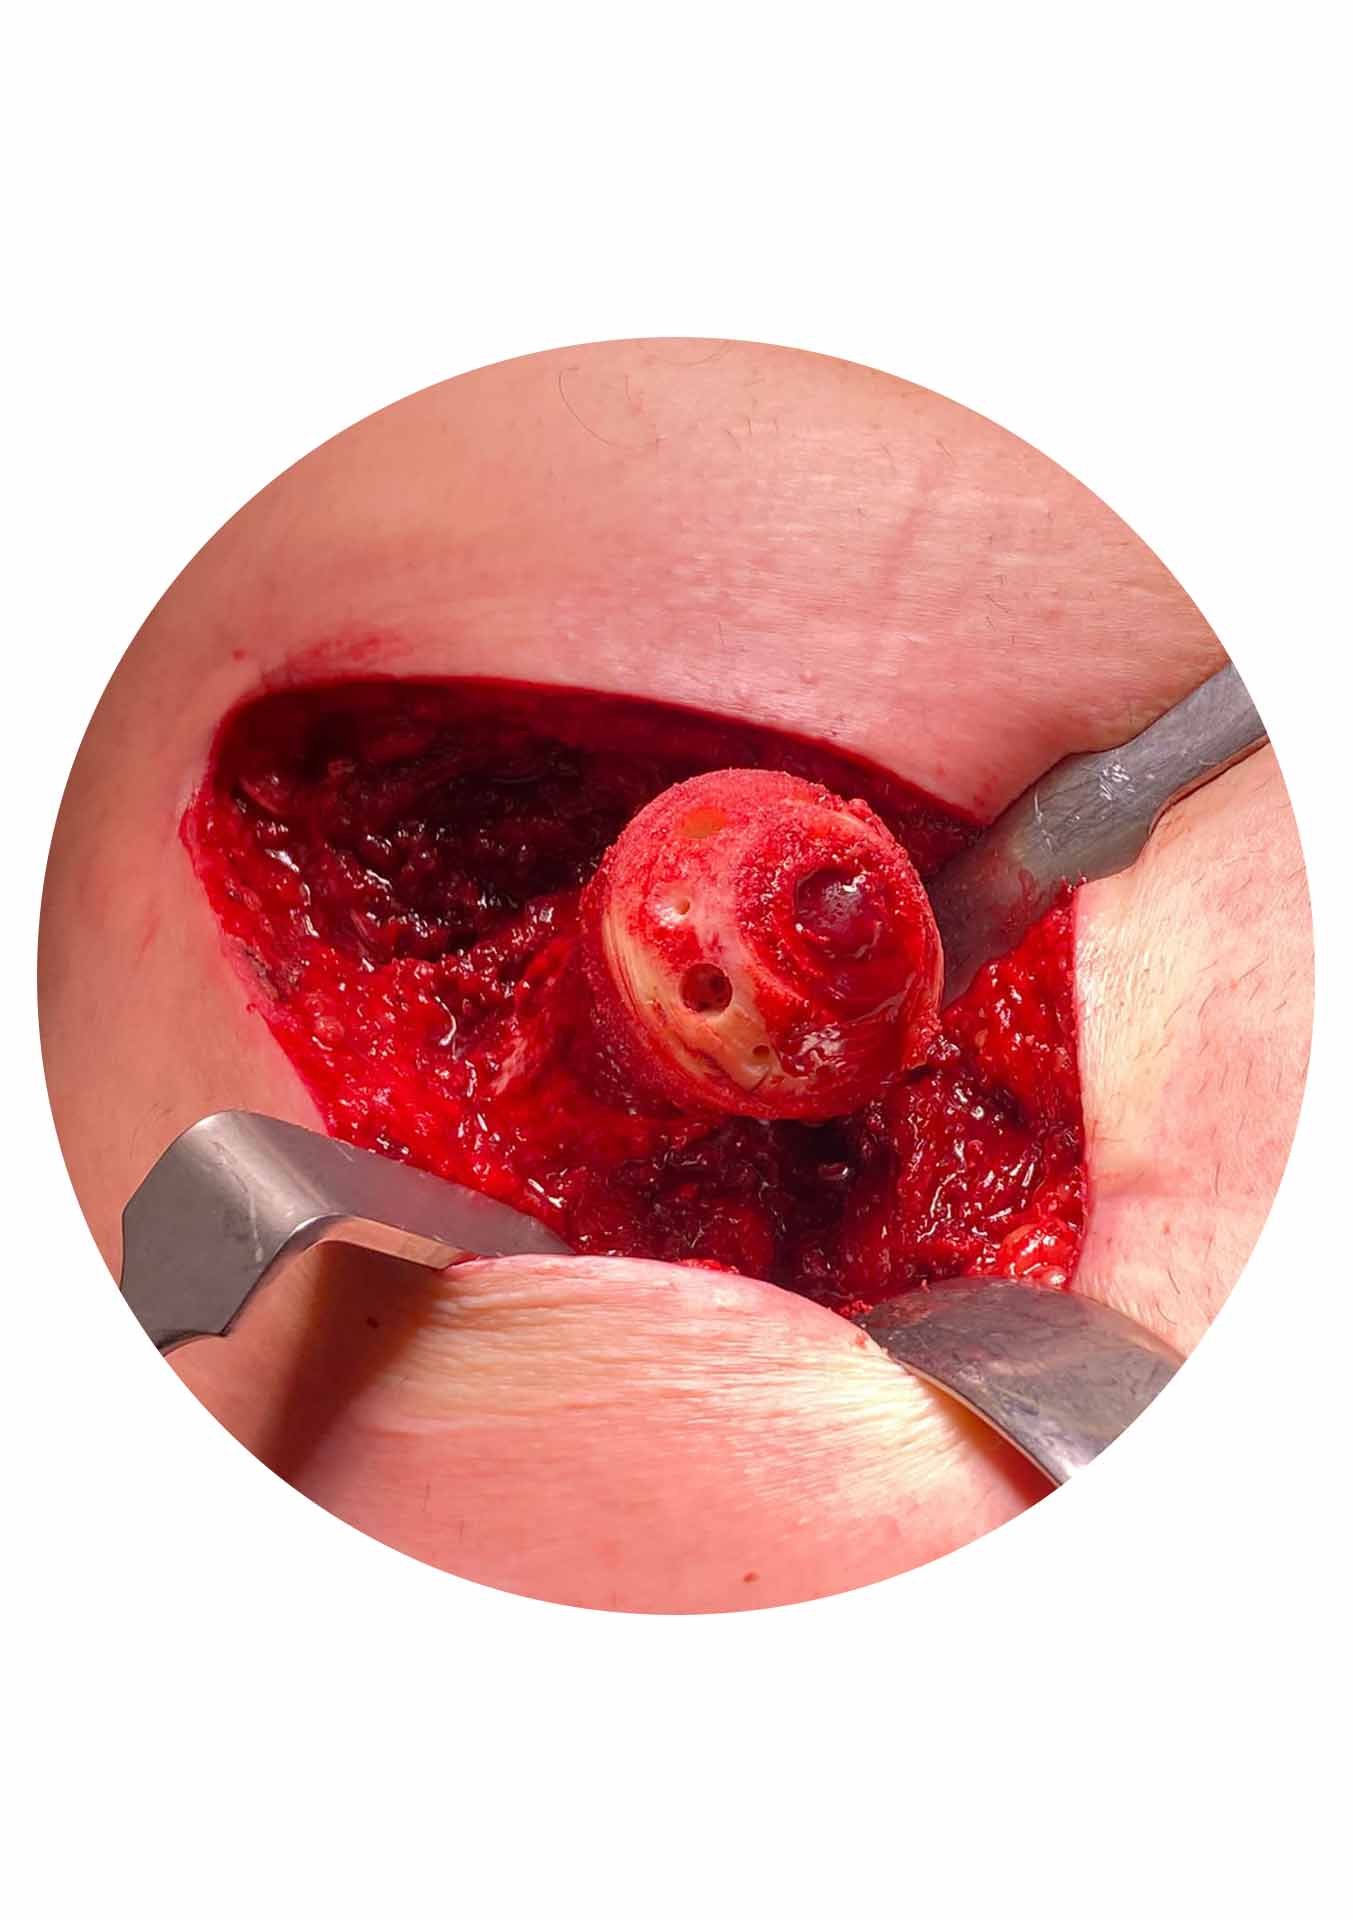

A Birmingham Hip Resurfacing (BHR) desenvolvida pelo cirurgião britânico Sir Derek McMinn tem mais de 20 anos de utilização com provas dadas em várias publicações e registos nacionais e internacionais. Tecnicamente a cirurgia é realizada por uma abordagem lateral (Hardinge – corte na face lateral da anca de cerca de 12 a 15cm) e é necessário deslocar (luxar cirurgicamente) a articulação para se puder “raspar” a cartilagem doente da cabeça do fémur e da cavidade acetabular para em seguida serem colocados, em sua substituição, uma cup acetabular e uma cabeça femoral ambos de metal. A BHR é portanto uma articulação metal-metal (MoM) sendo este metal o crómio-cobalto que tem uma história de utilização em Ortopedia de mais de 40 anos. A BHR é o resurfacing MoM da anca com maior sucesso a nível global e representa uma excelente solução para um grupo específico de doentes com artrose da anca com indicação cirúrgica.